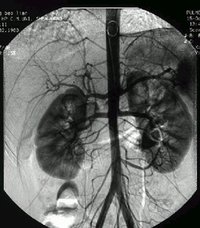

腦血管畸形1、腦動脈造影

腦動靜脈畸形有以下典型表現:①顯示畸形血管。這是特徵表現,呈一團管徑相仿相互糾纏的迂曲擴張血管。畸形血管團的範圍可小如指甲,大如手掌,多見大腦半球皮質.②異常粗大的供養動脈和引流靜脈伴局部循環加快。此為局部血流短路的表現。③血流分流現象:造影劑隨血流經畸形血管的短路大量流入靜脈,因此,血管畸形部分因血流量增加而顯影十分清楚。④血腫的表現:血管破裂出血致腦內血腫,血腫的主要表現為局部占位徵象,一股腦部動靜脈畸形無血腫時,腦血管不出現占位徵象,腦血管不移位。 2、CT表現:

5.腦血管造影:最可靠、最重要的診斷方法,動脈期可見血管團、供血動脈及早期顯現的引流靜脈。

4、腦血管造影是本病最可靠和主要的診斷方法,並能行血管內介入治療。